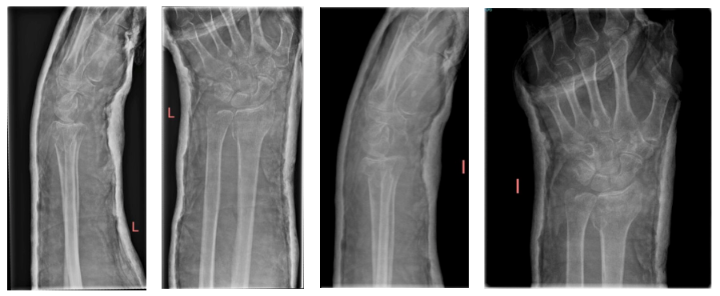

Fracture treated conservatively (February 2022).

One-week follow-up showed loss of height and mild TILD with neutral tilt.

The patient wore a forearm cast for 4 weeks (FEDR). A CT scan of the left wrist was performed, including axial views and coronal/sagittal reconstructions. The scan revealed:

• Comminuted fracture with impaction of the distal radius and ulnar displacement of the posterior-lateral cortical fragment

• Non-displaced fracture of the ulnar styloid process

• Generalized osteopenia

• No intra-articular loose bodies

• Subchondral sclerosis with cysts in the distal ulna

• Scaphotrapezoid degenerative changes with an intraosseous ganglion in the distal scaphoid

• Mild rhizarthrosis

• No other significant findings